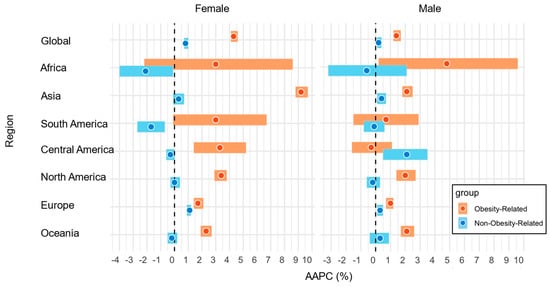

Global Incidence Trend of Early-Onset Obesity-Related and Non-Obesity-Related Cancers

by

Miyu Terashima, Kota Nakayama, Satoko Ugai, Hwa-Young Lee, Yuta Tsukumo, Etsuji Suzuki, Hiroki Mizuno, Minkyo Song, Naoko Sasamoto, Ichiro Kawachi and Tomotaka Ugai

Curr. Oncol. 2025, 32(6), 324; https://doi.org/10.3390/curroncol32060324 (registering DOI) - 31 May 2025

The global rise in obesity prevalence and the incidence of early-onset cancer (diagnosed between 20 and 49 years of age) is a serious public health concern. We, therefore, evaluated the recent global trends in the incidence of early-onset obesity-related cancers and compared them

[...] Read more.

The global rise in obesity prevalence and the incidence of early-onset cancer (diagnosed between 20 and 49 years of age) is a serious public health concern. We, therefore, evaluated the recent global trends in the incidence of early-onset obesity-related cancers and compared them to those of non-obesity-related cancers. We obtained age-standardized incidence rates of early-onset cancers diagnosed between 2000 and 2012 in 44 countries from the Cancer Incidence in Five Continents database. Using joinpoint regression models, we calculated the average annual percentage changes (AAPCs) and their corresponding 95% confidence intervals (95% CIs) for combined and individual categories of obesity-related cancers (11 and 9 cancer types in females and males, respectively) and non-obesity-related cancers (12 cancer types in both females and males). Differences in the AAPC were assessed by comparing 95% CIs, where nonoverlapping 95% CIs were considered statistically significantly different. We observed statistically significant positive AAPCs for early-onset obesity-related cancers in all available countries combined among females (global AAPC, 4.3%; 95% CI, 4.1–4.6%) and males (global AAPC, 1.4%; 95% CI, 1.2–1.7%). When analyzed by countries, we observed statistically significant positive AAPCs in 26 countries among females and 11 countries among males. AAPCs for early-onset obesity-related cancers were statistically significantly higher than those of non-obesity-related cancers in several regions, especially North America and Oceania. In conclusion, this study indicates that the incidence of early-onset obesity-related cancers exhibited a more pronounced increasing trend than non-obesity-related cancers among both sexes in many countries and regions.

Full article

Figure 1